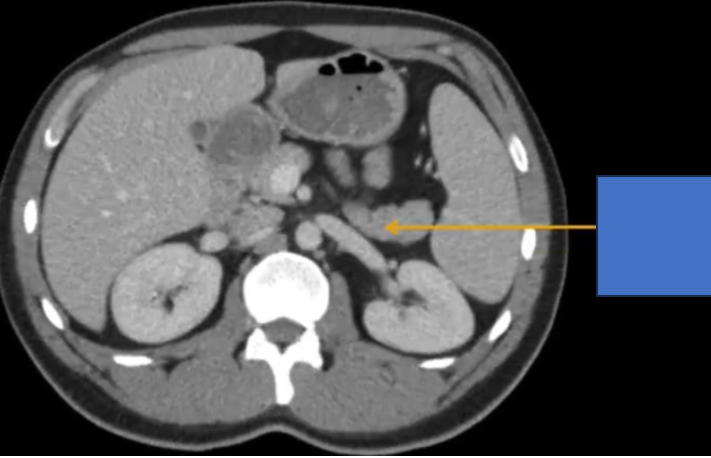

cq trong hình ?